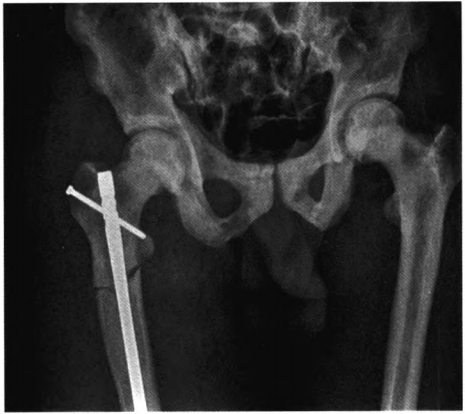

图3.术后骨盆正位X线片示骨折对位对线良好,内固定安全可靠

患者人院后给予消肿、镇痛、改善微循环等对症治疗,行骨牵引纠正骨折畸形。排除手术禁忌证后在腰硬联合麻醉下行右股骨骨折切开复位髓内钉内固定术。患者取平卧位,采用右大腿近端前外侧人路,显露骨折断端,探查见股骨转子下横行骨折,股骨近端髓腔相对较窄,骨质致密坚硬,多为硬化增厚的皮质骨,断端坎顿少量碎骨片及软组织,清理骨折断端,继而自切口内向近端逆行开口扩髓,再从股骨大转子自近端做纵行切口6 cm,依次切开皮肤皮下及阔筋膜张肌,自梨状窝开口处放人导针,借复位钳及牵引骨折复位后将导针插入股骨远端,近端扩髓至13 mm,远端扩髓至11mm,测量无误后放置lO mm*360 mm股骨顺行髓内钉,在C臂机透视下应用瞄准器锁人2枚远端锁钉,回敲加压断端,近端锁入1枚锁钉。手术历时2.5 h,术中出血量约250mL。定期复查股骨正侧位x线片,监测骨折愈合情况及石骨症病情进展情况(见图3~4)。

石骨症多无特异性的临床表现,多因外伤后骨折就诊,目前对于石骨症的确诊多依靠影像学检查。X线片中常见的有全身骨密度普遍增高、颅底硬化明显,椎体呈“夹心蛋糕样”特征性改变,两侧髂骨翼呈典型“同心环状征”,肋骨可呈“串珠样”改变等等。本例患者因跌倒后就诊,肢体外观并无异常性改变,诊断也主要靠影像学的特征性表现。成人石骨症合并骨折多可手术治疗,国内报道的数篇关于石骨症合并股骨近端骨折的手术方式多为锁定钢板固定及髓内固定。考虑因石骨症骨质致密且内部血管网稀疏,髓腔过于狭窄,扩髓钻孔的方式难以实现且可能发生医源性的再骨折,但此患者骨皮质硬化出现了少见的不对称性,右股骨骨皮质明显低于左侧,相对更易于实现扩髓操作,故此患者采用髓内固定的手术方式,从X线片和术中探查见右股骨远端骨皮质较近端逐渐增厚,不需阻挡钉辅助固定尾端。术后复查X线见内固定装置位置可,下肢力线良好,内固定装置无松动。